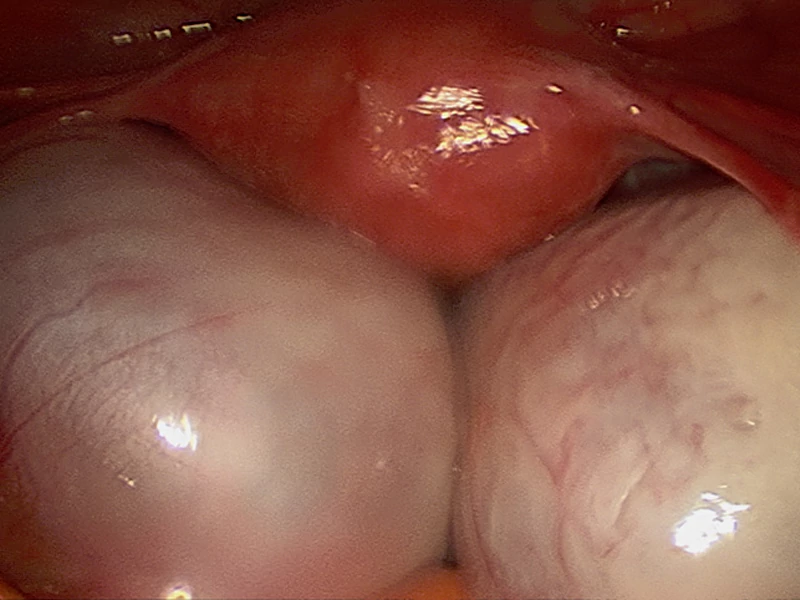

لاپاراسکوپی کیست تخمدان؛ درمان قطعی با کمترین آسیب

لاپاراسکوپی کیست تخمدان نوعی جراحی است که به منظور تشخیص و درمان کیستهای تخمدان استفاده میشود. این روش کم تهاجمی